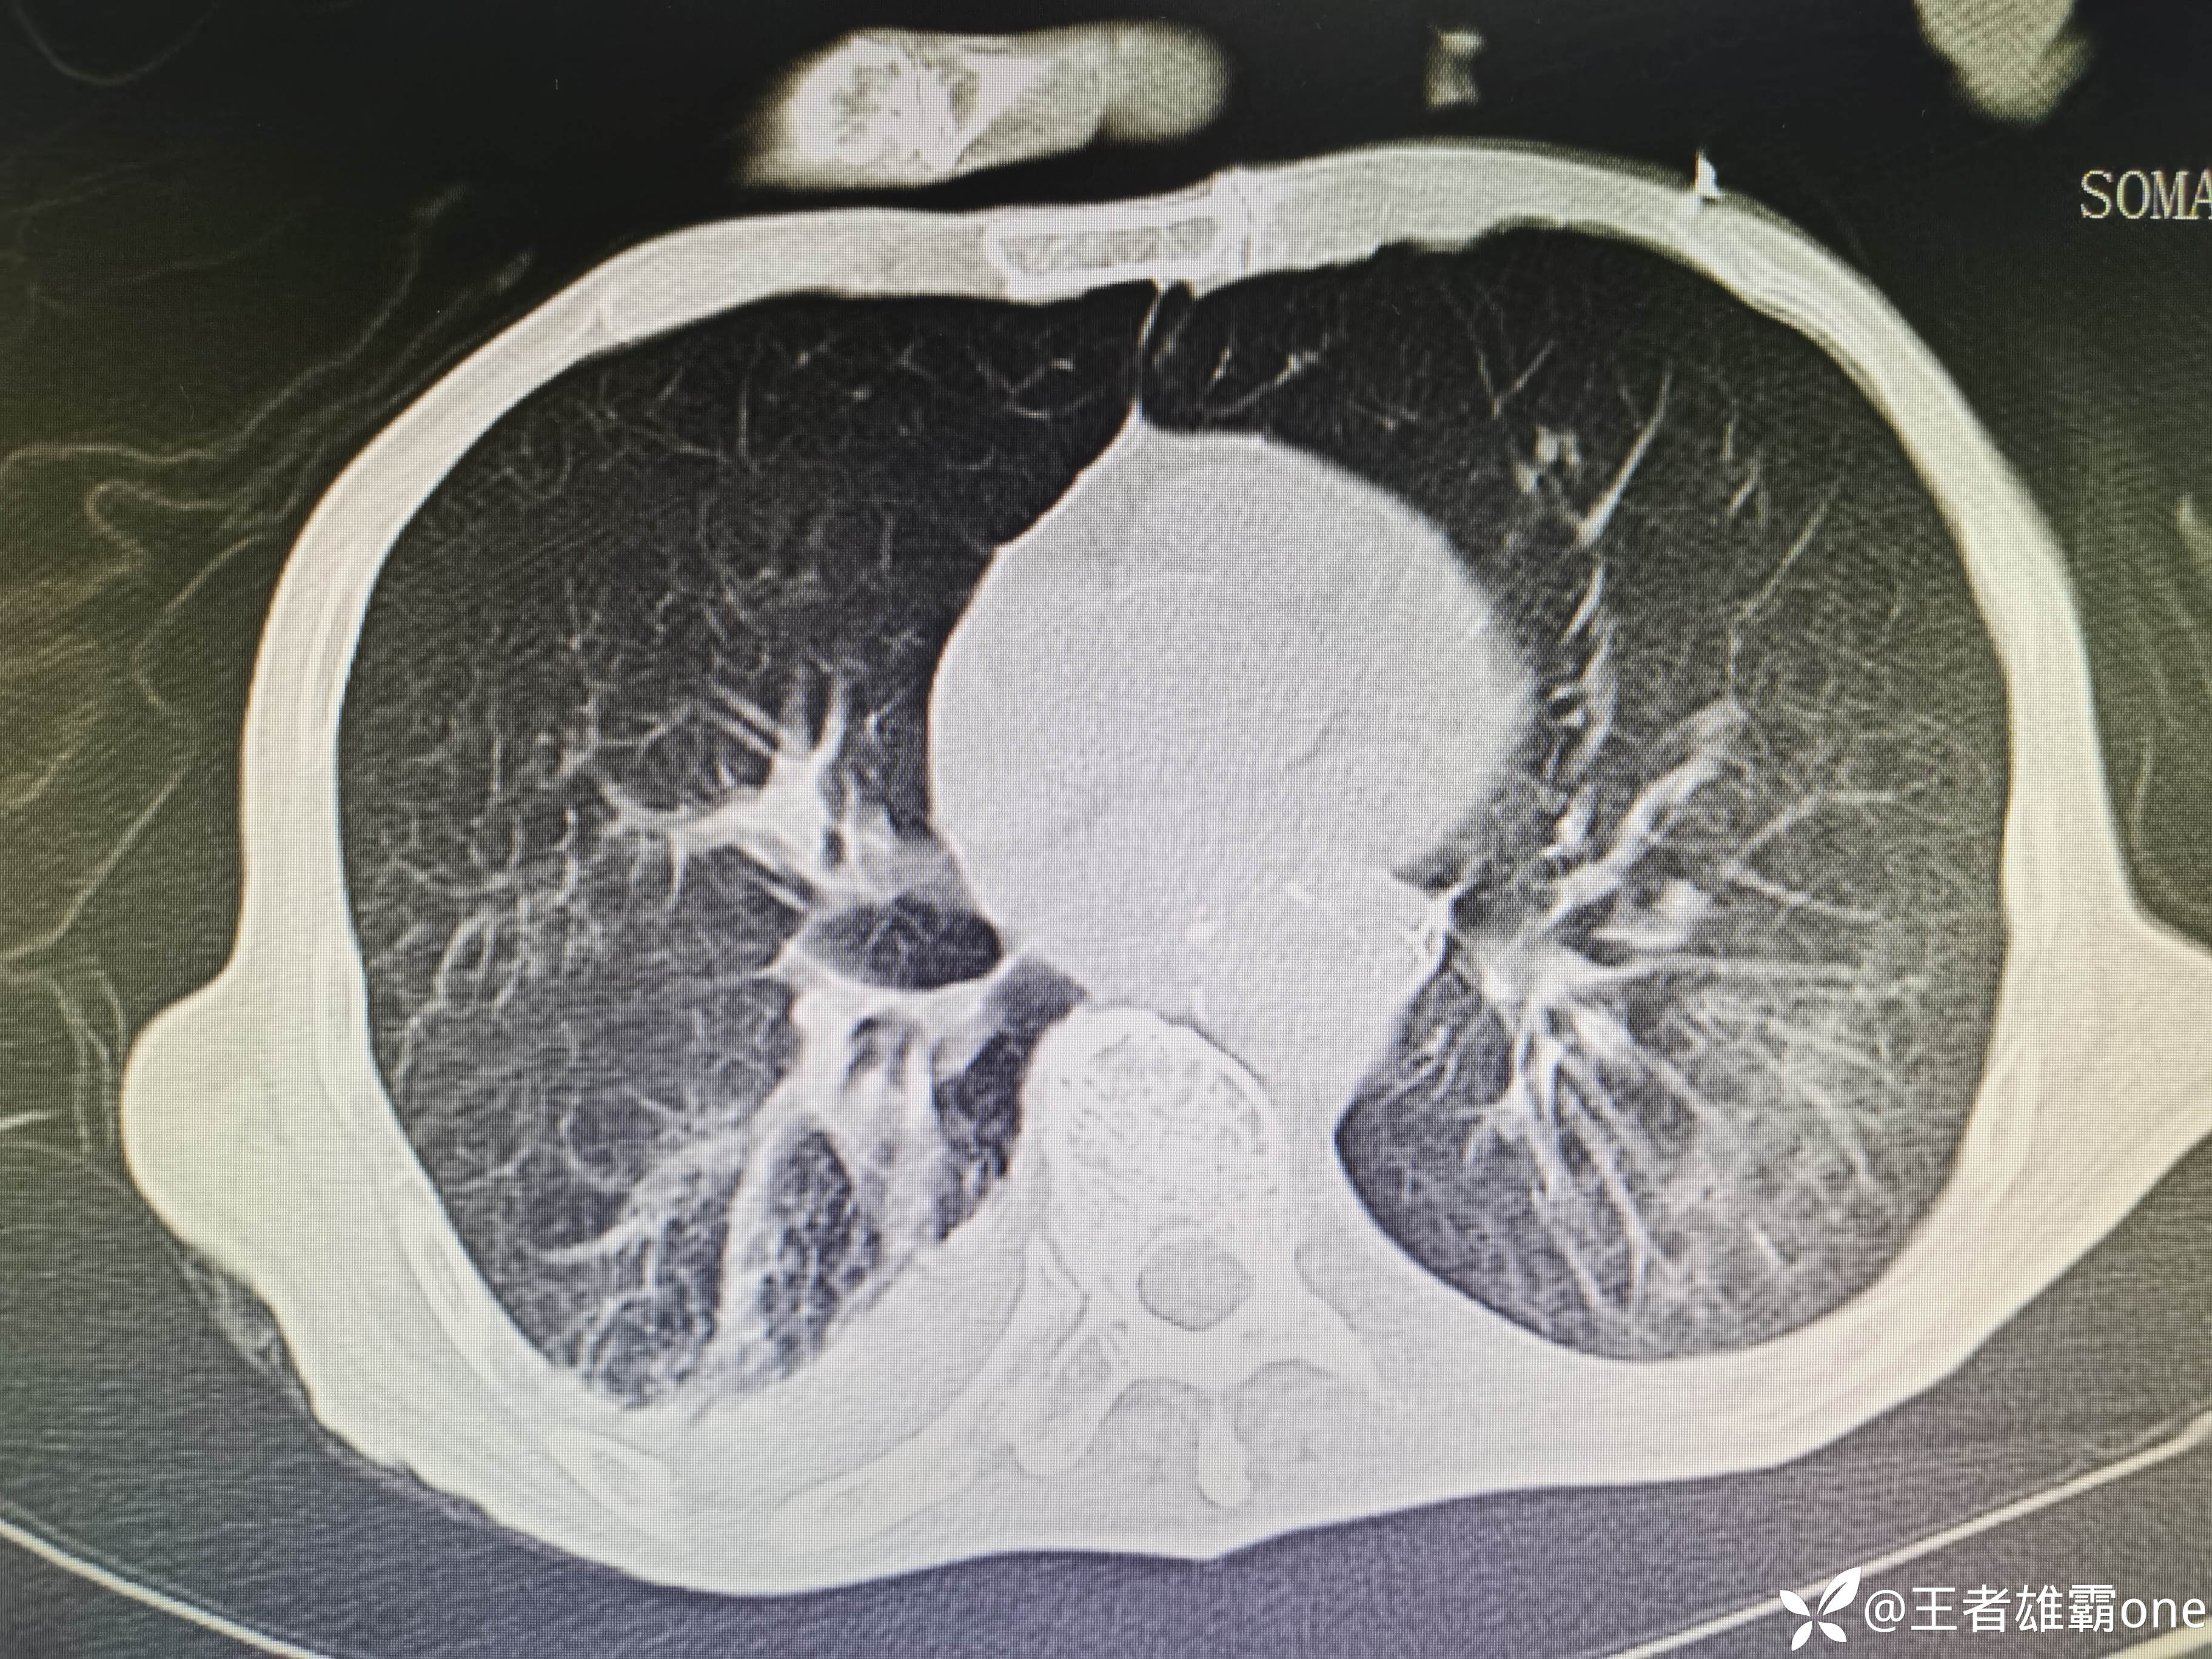

入院时胸部CT:

具体图片: